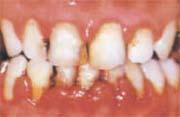

歯周炎の歯肉

(1)歯肉が退縮して歯根が露出

(2)歯がグラグラする

(3)膿が出る

(4)口臭がある